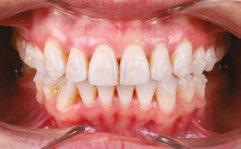

An OMD assessment with TMD muscle pain: a case study

Judith Dember-Paige, BSOHP, COM®, discusses how transformation sometimes takes years, but it’s worth the effort

Stan was referred to my office by a TMD specialist. His chief complaints were he could not chew or open his mouth without pain. It seemed the less he chewed, the more pain he experienced. As a result, an Orofacial Myofunctional Therapy (OMT) program was created to help support his muscles of the TMJ and craniofacial respiratory complex. He used his splint as instructed by his specialist. However, his anterior open bite widened, and his teeth became more misaligned over time.

Upon closer examination, there were contributing factors that led to his discomfort. Stan had been a stomach/face sleeper for years. He also bit his nails since childhood, had a smoking habit from his youth, and he was prone to ear infections. He had moderate tongue and buccal ties, obligate mouth breathing, aggravated by a deviated septum, narrow nares, low tongue resting posture, an anterior open bite, a lower jaw that deviated upon opening, and bouts of acid reflux.

When the tongue rests in the palate, it impacts facial development especially for children who are still growing. An adult, for example, like our friend Stan, the progress made is gradual but more likely to last a lifetime. Generally, therapy starts out once a week for about 2-3 months. Then therapy progresses to every other week for 2-3 months, and then changes to once a month for about 5 months for the rest of the year. The exercises are done a minimum of 2 times everyday. These exercises are designed to strengthen and tone the orofacial muscles, building brand new neuromuscular function. When the muscles of the face are well developed, it may favorably impact appearance and the overall integrity of the facial structures. The muscles of the face also include the tongue, lips, cheeks and neck. Although the therapy program is typically only a year, Stan really liked how good he felt and decided to continue with some of the exercises to this day. From the photos you can see how much the program has impacted his health and well-being.

During his therapy, there was a discussion about the possible benefits he may receive from having his jaws expanded, making more room for his tongue, then to be followed by a tongue and buccal frenums release. His intermolar width is 34 mm, and his intercanine width is 25 mm. I feel any expansion has a potential benefit.

To document any initial assessment, the midpoint of therapy, and when therapy has ended, it is important to take detailed photos, videos, plus full measurements of the face and teeth. This makes it possible to compare results while showing that your therapy works based on the evidence you gathered before, during, and after treatment.

Figure 5

Figure 6: No room for his tongue

Figure 4: 7 years later on April 10, 2024. Anterior open bite closed a bit

Figure 2: Initial assessment on December 15, 2016 (top left). Later September 20, 2017, his anterior openbite widened (top right)

Figure 3: Milled orthotic splint